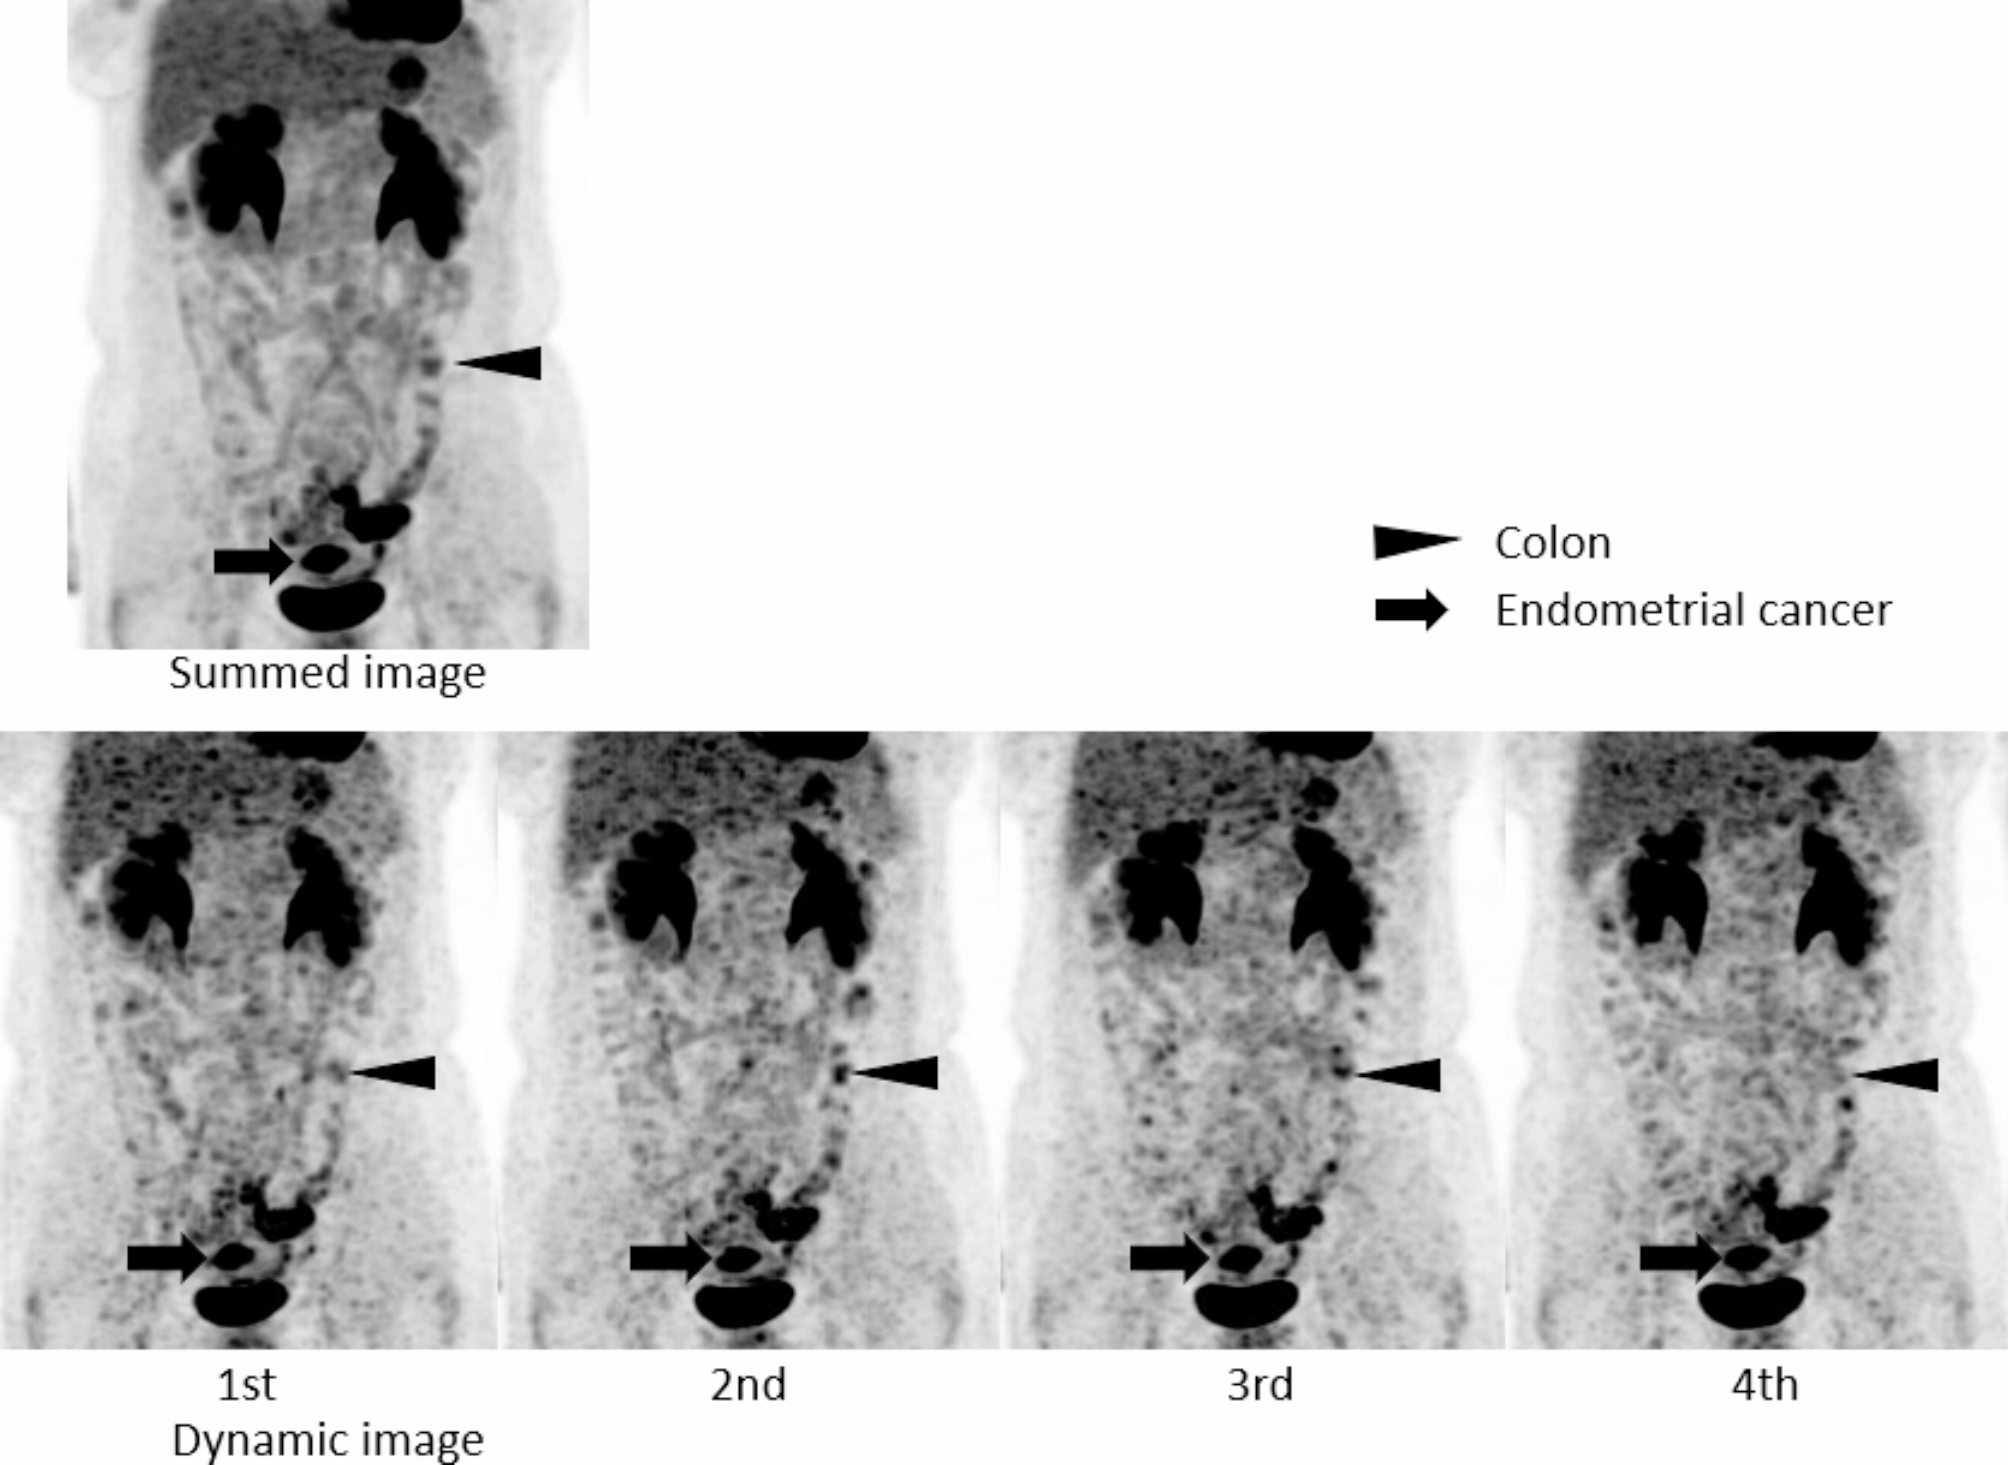

Summed image and four serial whole-body dynamic PET images (1st − 4th, 3 min each) of a patient with endometrial cancer (arrows). One focal uptake is observed in the left abdomen in the summed image, and the uptake disappears in 4th phase (arrowheads). This one was clinically diagnosed as physiological uptake in the colon.